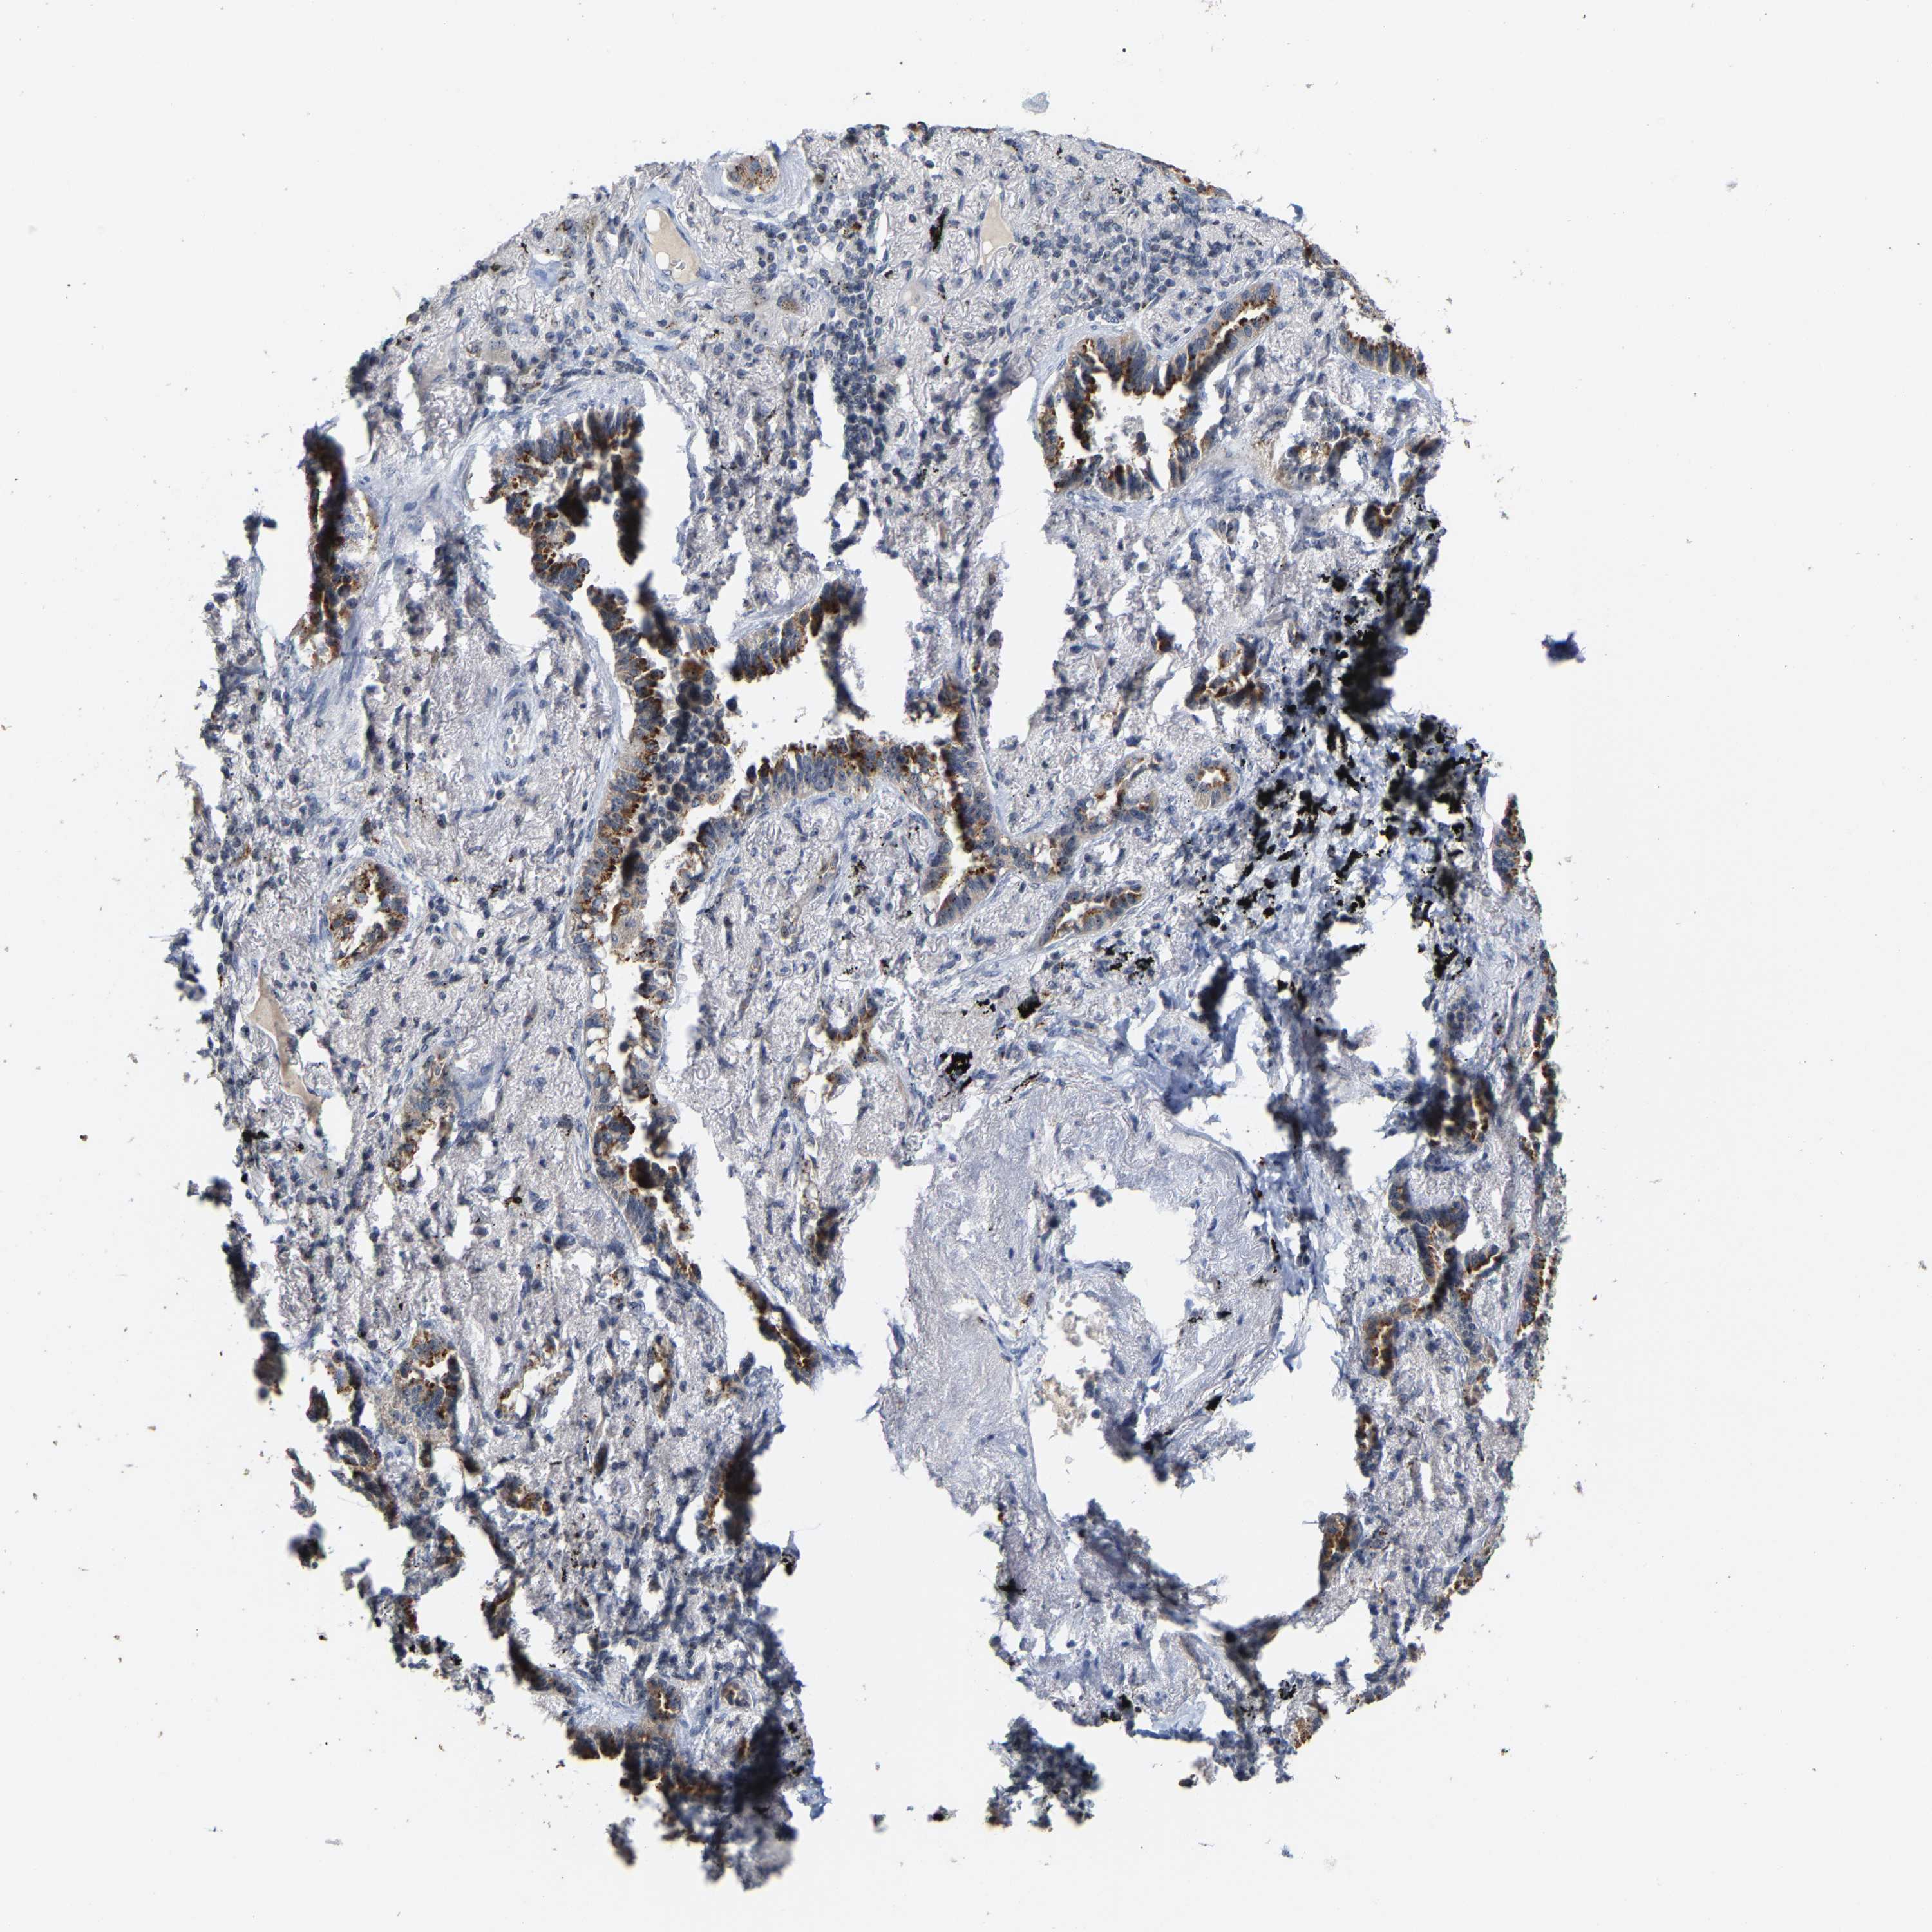

LUNG ADENOCARCINOMA (VALIDATION) - Interactive survival scatter ploti

The Survival Scatter plot shows the clinical status (i.e. dead or alive) for all individuals in the patient cohort, based on the same data that underlies the corresponding Kaplan-Meier plots. Patients that are alive at last time for follow-up are shown in blue and patients who have died during the study are shown in red.

The x-axis shows the expression levels (FPKM) of the investigated gene in the tumor tissue at the time of diagnosis. The y-axis shows the follow-up time after diagnosis (years). Both axes are complimented with kernel density curves demonstrating the data density over the axes. The top density plot shows the expression levels (FPKM) distribution among dead (red) and alive patients (blue). The right density plot shows the data density of the survived years of dead patients with high and low expression levels respectively, stratified using the cutoff indicated by the vertical dashed line through the Survival Scatter plot. This cutoff is automatically defined based on the FPKM cutoff that minimizes the p-score. The cutoff can be changed by dragging the vertical line or by entering a cutoff value in the square labeled "Current cut-off".

Under the Survival Scatter plot the p-score landscape (black curve; left axis) is shown together with dead median separation (red curve; right axis). Dead median separation is the difference in median mRNA expression between patients who have died with high and low expression, respectively. It is calculated as follows: median FPKM expression of dead patients with high expression - median FPKM expression of dead patients with low expression. This is intended to aid the user in visually exploring custom cutoffs and the associated p-scores and dead median separation.

Individual patient data is displayed and can be filtered by clicking on one or more of the category buttons on the top of the page. Categories describing expression level and patient information include: high, low, alive, dead, female, male and tumor stages. The scale of the x-axis can be toggled between linear and log-scale by clicking on the "x log" button. Mouse-over function shows TCGA ID, patient information and mRNA expression (FPKM) for each patient.

& Survival analysisi

Kaplan-Meier plots summarize results from analysis of correlation between mRNA expression level and patient survival. Patients were divided based on level of expression into one of the two groups "low" (under cut off) or "high" (over cut off). X-axis shows time for survival (years) and y-axis shows the probability of survival, where 1.0 corresponds to 100 percent.

NOP58 is not prognostic in Lung Adenocarcinoma (validation)

: 73.73

P scorei

N/A

Average pTPM 67.9

Number of samples 105